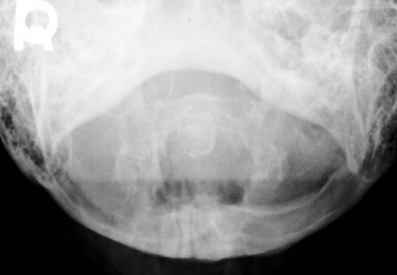

1. What is the key finding?

2. What is the etiology of the main finding - trauma, congenital, other?